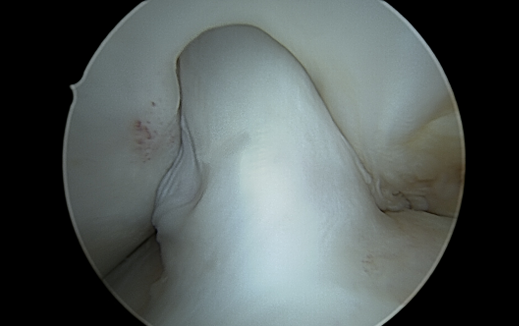

Op deze dag voerde Jacco Zijl een uitgebreide nochplastiek uit. Hij noemde mijn ‘notch’ een ‘notchje’. Die kruisband paste er niet in. Op de operatietafel werd er na de notchplastiek een foto gemaakt van de hyperextensie die ik haalde. Ik was zo blij als een klein kind. Dít moet het zijn. Na een wat moeizame start met een forse nabloeding ging ik goed vooruit. Twee weken na de operatie liep ik zelfs voor het eerst een klein blokje buiten met een normaal dynamisch looppatroon. Niet pijnvrij, maar dat deed er op dat moment niet toe. Ik huilde tranen van geluk. De winterstop? Dat moest mogelijk zijn!

| Hyperextensie na notchplastiek |